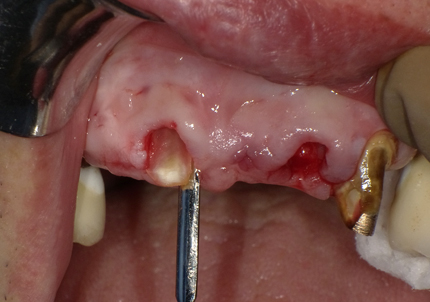

11.舌側歯牙片の抜歯

【右上1番SST 口蓋側歯根の抜歯】

【左上2番 SST 口蓋側歯根の抜歯】